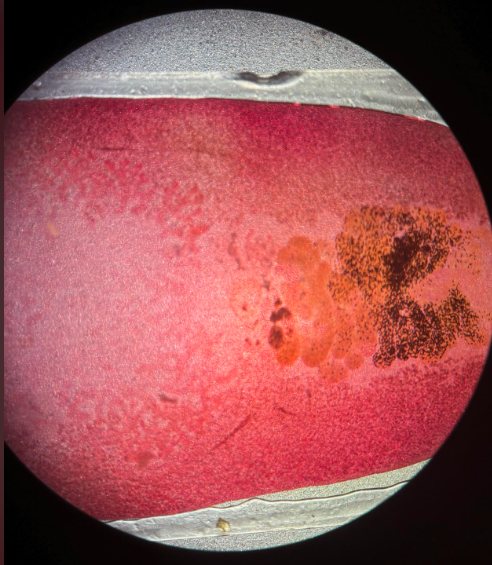

plasmodium falciparum stadia schizogonii krwinkowej

plasmodium falciparum stadia schizogonii krwinkowej